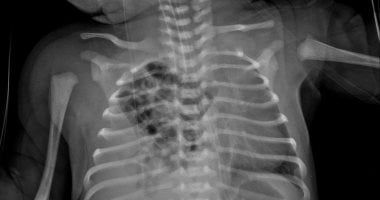

فى إنجاز طبى جديد يُضاف إلى سجل النجاحات المتميزة لقطاع الصحة بالمنوفية، نجح الفريق الجراحى بمستشفى زاوية الناعورة المركزى بقيادة الدكتور مجدى لولح والفريق المعاون له تحت إشراف الدكتور إسلام الفقى مدير المستشفى، فى إجراء عملية نادرة لإصلاح فتق بالحجاب الحاجز من نوع بوكدالك فى الجهة اليمنى، وهى من الحالات شديدة الندرة التى لا تتجاوز نسبتها عالميًا 10–15% من إجمالى حالات الفتق الحجابى الخلقى،تنفيذًا لتوجيهات الدكتور خالد عبد الغفار نائب رئيس مجلس الوزراء ووزير الصحة والسكان و اللواء إبراهيم أبو ليمون محافظ المنوفية بتقديم خدمات صحية ذات جودة عالية تلبى احتياجات المواطنين وتنفيذًا لتعليمات الدكتور عمرو مصطفى محمود وكيل بالمنوفية بالإرتقاء بمستوى الخدمات الطبية المقدمة للمواطنين بجميع أنحاء المحافظة.

وخلال العملية الدقيقة، تبيّن وجود الفص الأيمن من الكبد داخل التجويف الصدرى إلى جانب الأمعاء الدقيقة والغليظة، مما تسبب فى ضغط على الرئة اليمنى.

قام الفريق الطبى بإرجاع جميع الأعضاء إلى وضعها الطبيعى داخل تجويف البطن، ثم إصلاح الفتق بخيوط غير قابلة للذوبان من نوع "إيثيبوند" لضمان المتانة واستقرار الحالة.

كما لاحظ الجراحون وجود التصاقات وأغشية تليفية من نوع "لادز" أدت إلى التواءات بالأمعاء، فتم التعامل معها بتقنية إصلاح لادز الجراحية، والتى شملت إزالة الأغشية التليفية، وإعادة ترتيب الأمعاء الدقيقة إلى الجهة اليمنى والقولون إلى الجهة اليسرى، مع استئصال الزائدة الدودية كإجراء وقائي.